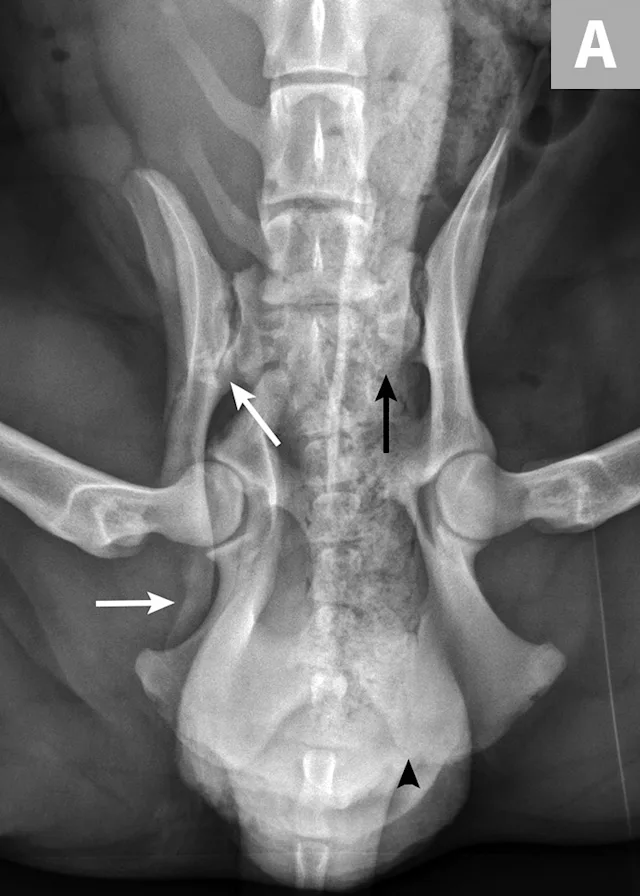

There are many different types of pelvic fracture configurations, and nearly half of pelvic injuries in dogs and cats involve fractures of the ilium.3,4,7,8 Clinically significant fractures involve the weight-bearing axis of the pelvis that includes the ilium and acetabulum (Figures 1-3). Although not a fracture, sacroiliac luxation is potentially significant because the sacroiliac joint is a component of the weight-bearing axis of the pelvis. Unilateral or bilateral fractures or luxations may occur, and it is common for patients to have a combination of pelvic injuries.3,4,7,13

FIGURE 1A

An 11-year-old intact female Welsh corgi with injuries of the weight-bearing axis of the pelvis. Ventrodorsal (A) and lateral (B) projection images show a left sacroiliac luxation with cranial and ventral displacement (black arrow). Pubic fracture with lateral displacement (dashed arrow) and an oblique tibial fracture (white arrows) were additional comorbidities. The tibial fracture was treated surgically with an internal plate fixation, and the pelvic injuries were managed conservatively.